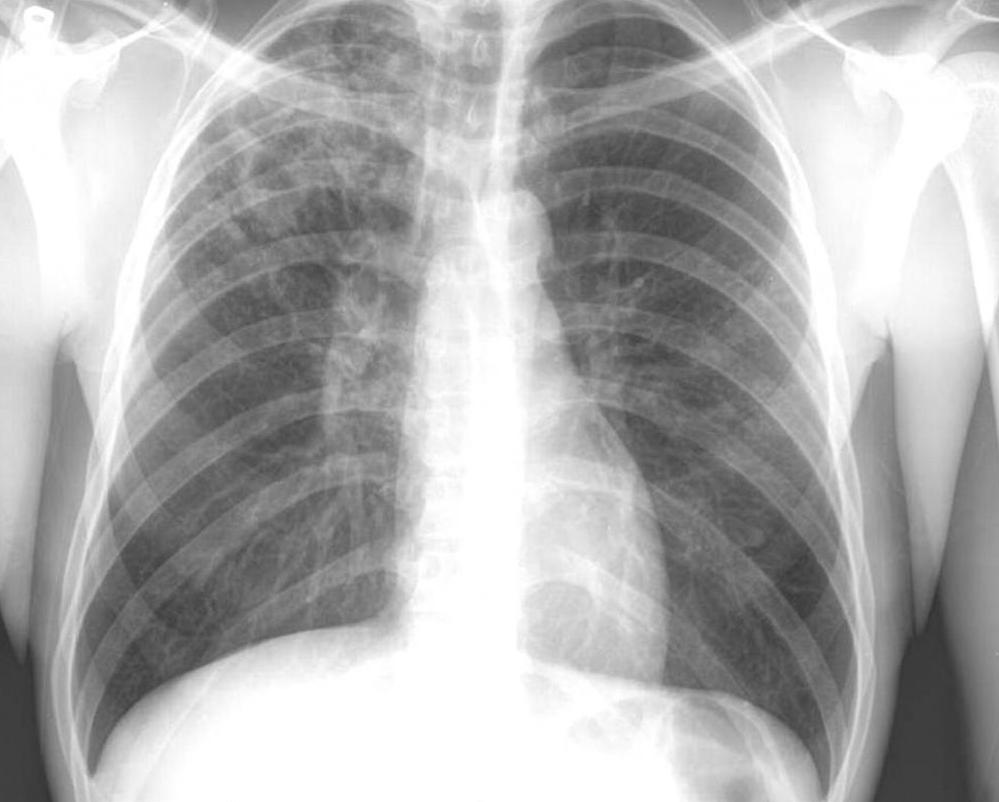

Уплотнение корней — один из наиболее часто встречающихся рентгенологических синдромов, который врач-рентгенолог определяет на обзорной рентгенографии грудной полости. Что это означает: «уплотнены корни легких»? Какие заболевания и патологические состояния скрываются под этой фразой?

Корни легких тяжисты и уплотнены: что это означает?

Как было отмечено выше, наиболее часто данный рентгенологический синдром встречается при хроническом бронхите курильщика и профессиональных заболеваниях легкого. Однако данный симптом может определяться и при острых воспалительных заболеваниях дыхательных путей, онкологических заболеваниях.

Данные тяжи представляют собой волокна соединительной ткани, которые тянутся от корня к периферии. Тяжистость обычно совмещается с расширением и уплотнением корня.

Не обладая высокой специфичностью, данный синдром позволяет врачу заподозрить определенную легочную патологию и направить пациента на дальнейшие обследования.

Корни легких малоструктурны и уплотнены: что это значит?

Нарушение структуры корня легкого, то есть невозможность отличить сосуд от бронха, появление затемнения на корне, обычно встречается при первичном туберкулезе, онкологических процессах.

На рентгенограмме при обширном туберкулезе или центральном раке легкого вместо корня может визуализироваться тень различных контуров, представляющая собой очаг (до 10 мм диаметром) или инфильтрат (более 10 мм). Данный симптом может также сочетаться с уплотнением, что обычно бывает при отложении солей кальция или обызвествлении (петрификации). Обызвествление является признаком хронического, долго протекающего процесса.

image

Таким образом, всего один рентгенологический симптом (в легких корни фиброзно уплотнены и тяжисты) может помочь заподозрить множество заболеваний: от обычного бронхита до рака легкого. Конечно, не стоит забывать, что рентгенография должна дополняться другими методами обследования: компьютерной томограммой, биопсией, посевом мокроты, бронхоскопией и так далее. Дополнительные методы обследования выполняются по назначению врача в зависимости от пути его диагностического поиска. Необходимо помнить, что только комплексное обследование поможет поставить правильный диагноз.